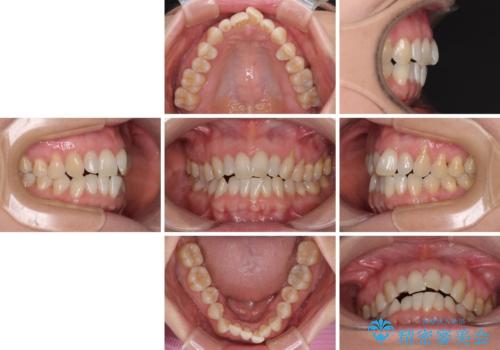

- 前歯の上下スペースによる食べにくさを気にして来院された患者様です。

インビザラインにより上下の前歯の隙間を閉じていくこととしました。

舌の突出癖があると上下前歯にスペースが開くため、矯正治療を機会に舌癖を改善するトレーニングを行ってもらい、矯正治療後の後戻りを防止するように指導しています。